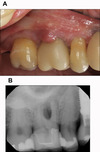

Marginal bone loss AND apical radiolucency affecting same tooth – diagnosis?

• Laesio endodontico-parodontica (endo-periodontal lesion).

• Treatment: Prognosis-dependent